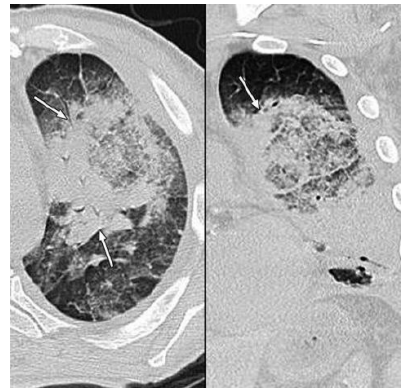

Q

Sinais e padrões torácicos

Qual o sinal apresentado da imagem?

A

Sinal do Halo Invertido

Consolidações periféricas cirundando opacidades em vidro fosco